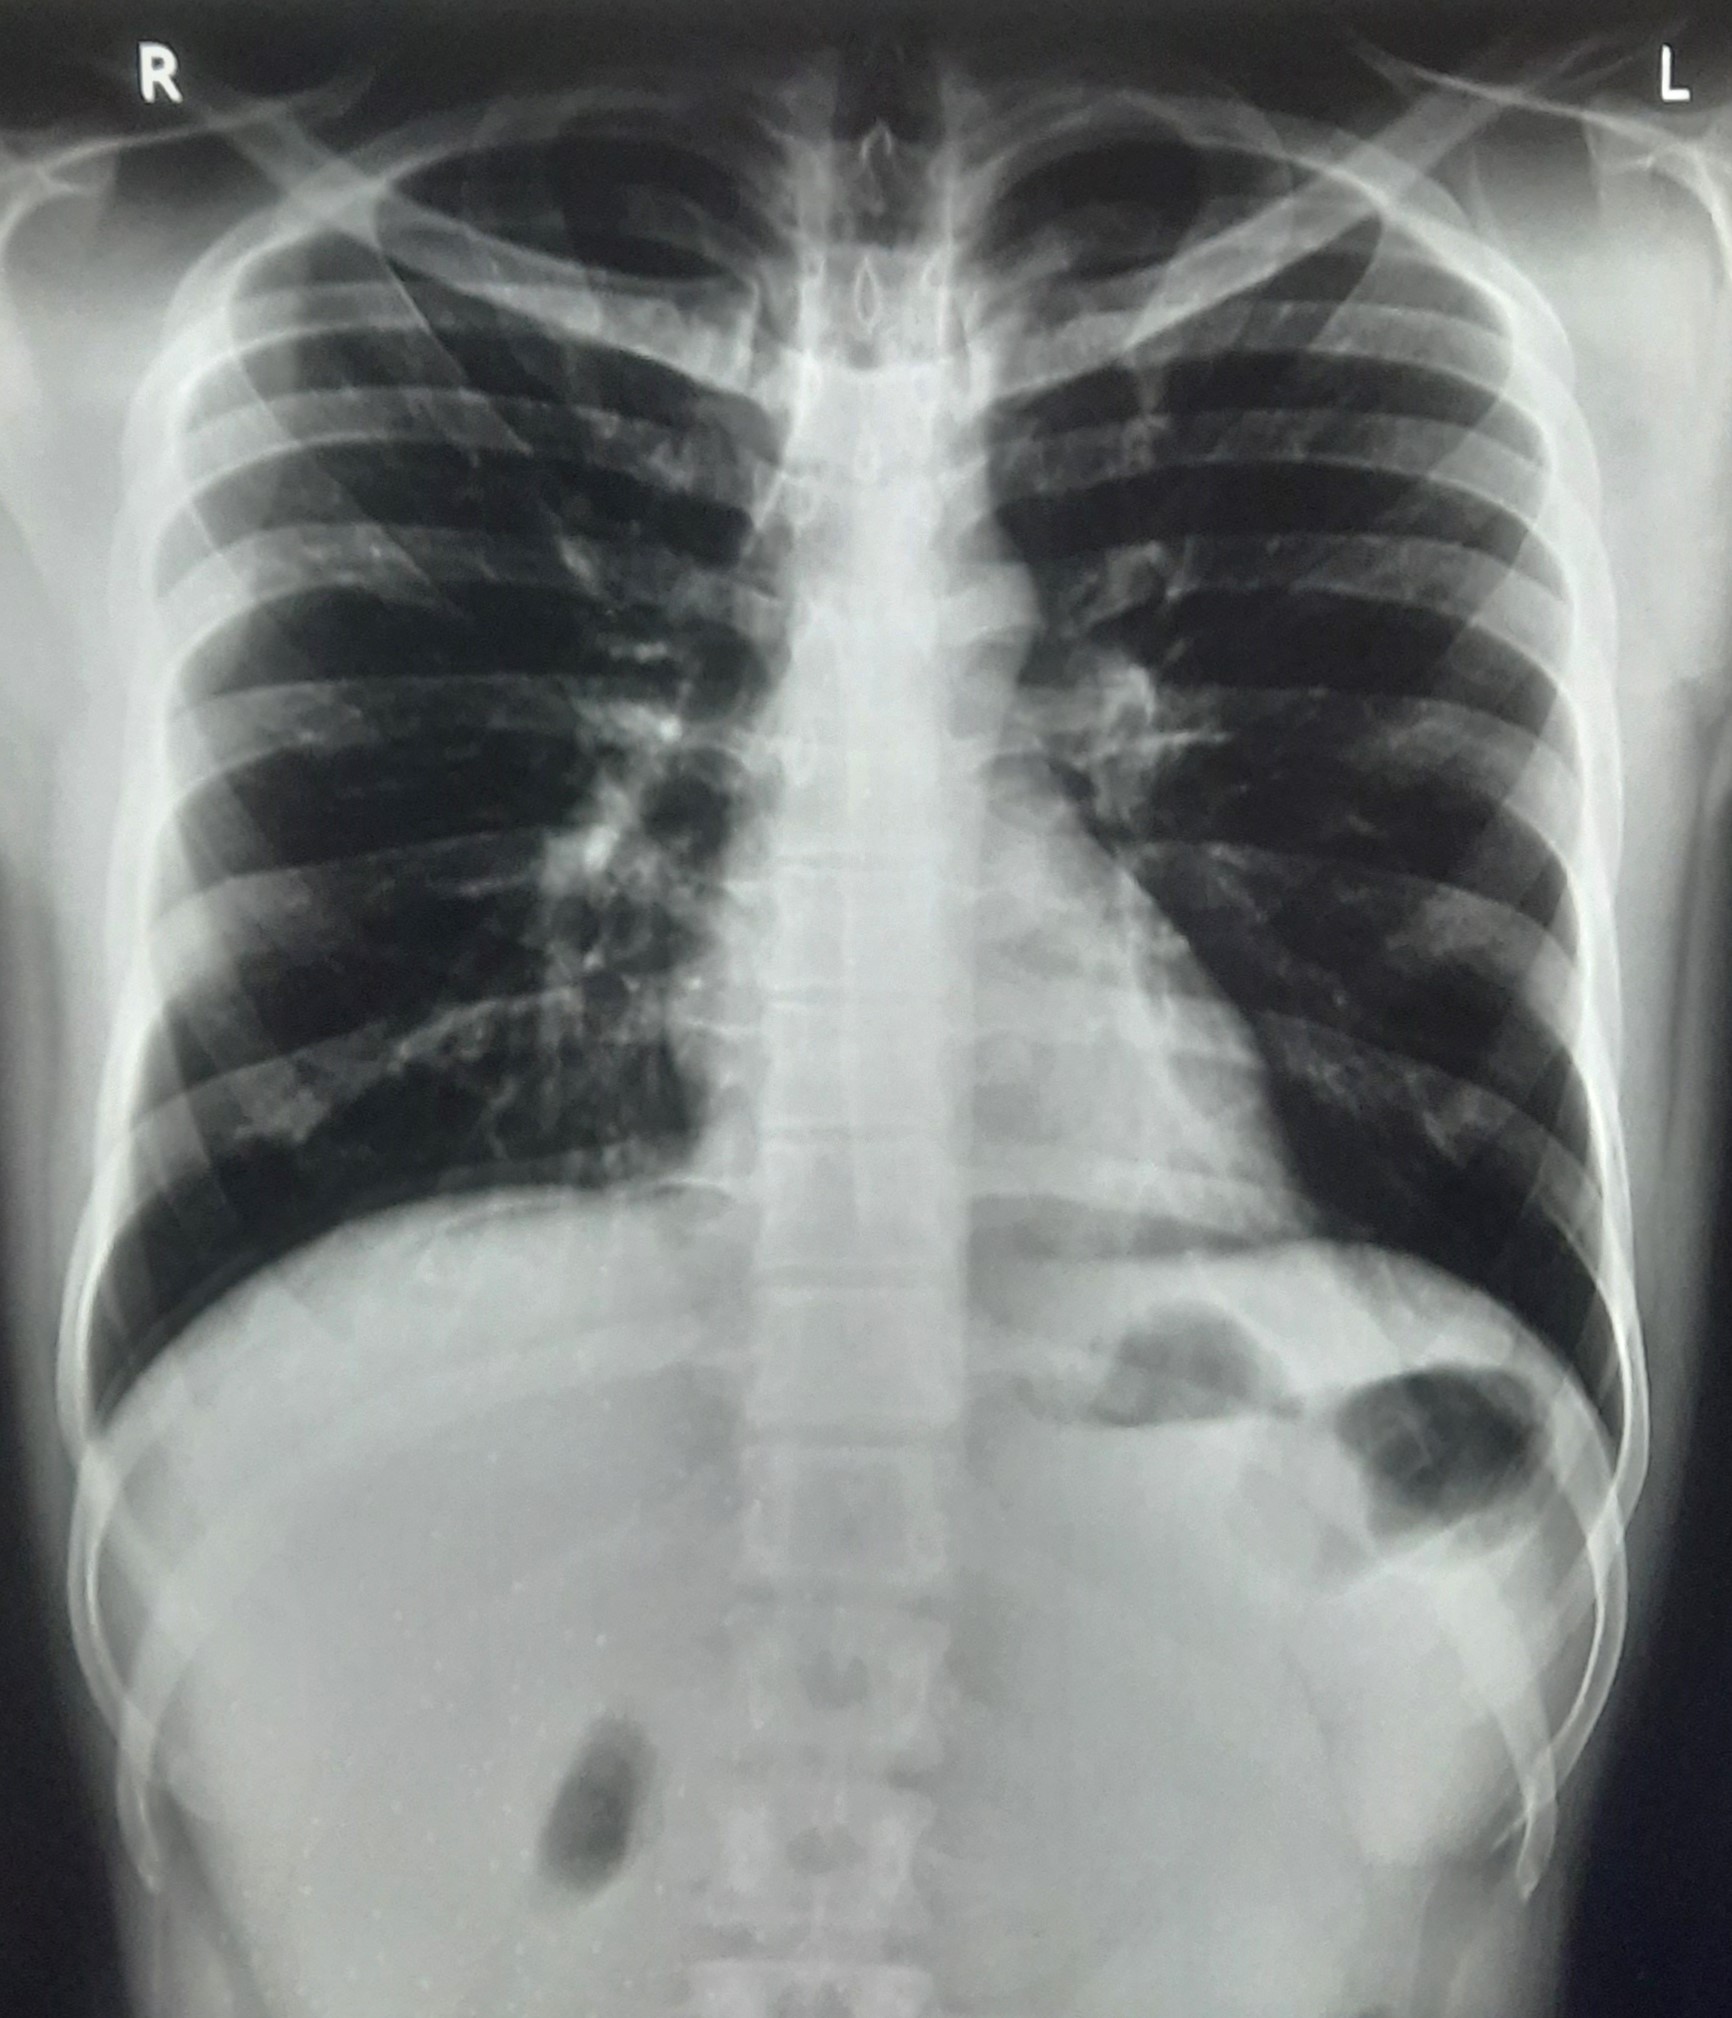

| 251 | IGGMC, Nagpur, Nagpur | P2 | 29-4221 | Ganpat Gaikawad | Consent taken on Paper | 70 Yrs. |

Provisional Diag : post TB sequele?

Final Diag : Fibrosis |

Non-TB Case (Confirmed) | Fibrosis | Abnormality visible on x-ray |